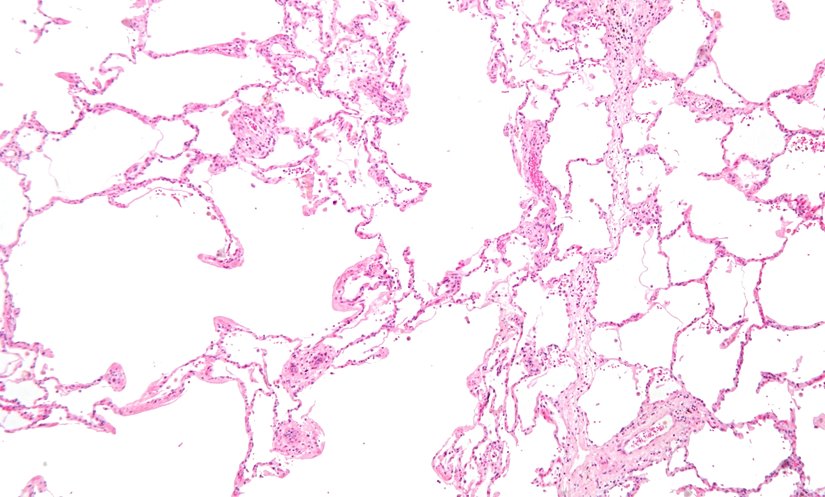

Resmin solunda şiddetli amfizem (büyük boş alanlar) görülmektedir. Görüntünün sağındaki akciğer dokusu alveollerin göreceli olarak korunmasına sahiptir. Görüntünün üst kısmı plevral (göğüs boşluğunu içten kaplayan ve akciğerleri çevreleyen, iki katlı, ince bir zar tabakası) yüzeye çok yakındır.